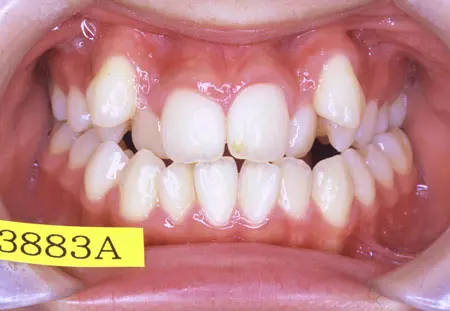

2024.08.1720代女性「前歯のガタガタが気になる」ワイヤー矯正で治療した症例